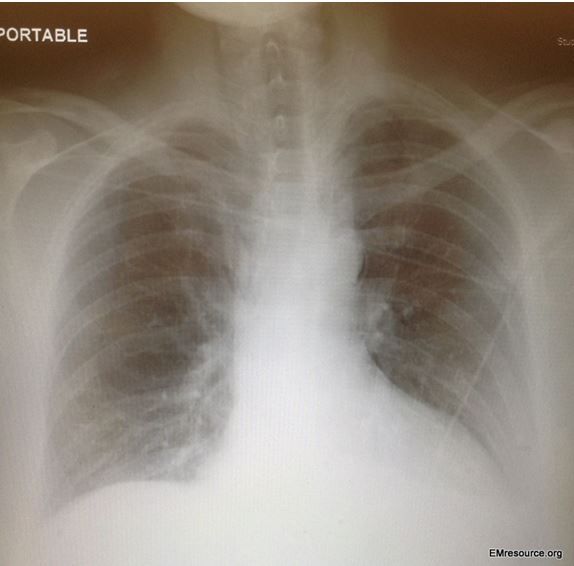

Chest x-ray, PA view (click to enlarge)

A screening ECG is performed to evaluate the patient’s chest pain and shows a normal sinus rhythm at a rate of 71 beats/min with nonspecific ST changes. Result of blood tests, including a CBC, metabolic panel, troponin, LFTs, and lipase, are all essentially normal as well. His chest x-ray film is shown in the Figure above (please click on image to enlarge).

The abnormal findings on this x-ray film could be easily overlooked. There is air in the deep neck, which can be seen as a lucent vertical stripe on both sides between the mandible and the first rib near the lateral edges of the cervical vertebrae. There is also a small area of air just to the left of the aortic arch. These findings are subtle.